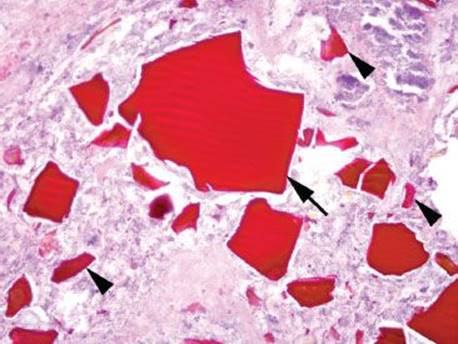

Mucosal calcium deposition is classified as metastatic, dystrophic, or idiopathic.189–192 Metastatic calcinosis is the most common subtype and refers to calcium deposition in normal tissues in the setting of calcium dysregulation. Other reported associations include hyperphosphatemia associated tumor lysis syndrome, atrophic gastritis, hypervitaminosis A, organ transplantation, gastric neoplasia, uremia with eucalcemia/euphosphatemia, and the use of aluminum-containing antacids, citrate-containing blood products, isotretinoin, and sucralfate.191,192 Dystrophic calcification refers to calcium deposition in damaged tissues in the setting of a normal serum biochemical environment. The incidence of mucosal calcinosis is unknown, but it is seen with some regularity in patients with renal failure or parathyroid dysregulation. Endoscopically, mucosal calcinosis appears as small white flecks, plaques, or nodules (Fig. 2.244). Histologically, the coarse black pigmentation is usually superficial and extracellular (Figs. 2.245–2.248). On histologic grounds alone, the calcium pigment can be difficult to distinguish from iron pill pigment since both can have brown-black tinctorial properties, and they both show a predilection for the superficial extracellular compartment. In difficult cases, a von Kossa special stain for calcium (calcium appears black) and a Prussian blue special stain for iron (iron appears blue) can be helpful. Not surprisingly, in this age of polypharmacy and an aging baby-boom population, some patients are found to have a conglomerate of both calcium and iron, making it worthwhile to perform both special stains when in doubt. Recognition of this deposit is important because “metastatic calcinosis” can indicate the patient is at risk for cardiac calcium deposits, which can be fatal. In addition, this diagnosis should prompt the clinician to search for causes of calcium dysregulation which can sometimes be obvious (as in the case of renal failure) but can occasionally be sneaky (as in the case of an occult parathyroid neoplasm or surreptitious antacid abuse).

Figure 2.245 Mucosal calcinosis. This case originated from a 79-year-old diabetic patient with renal failure and abdominal pain. Focal calcium deposition is seen (arrowheads); they appear chunky and deeply purple. Occasionally, the calcifications present a problem for the histology technicians: the tissue blocks can be especially difficult to cut and, consequently, “tissue holes” result from calcifications lost during processing. A confirmatory von Kossa special stain was positive, supporting the previously mentioned diagnosis.

Figure 2.246 Mucosal calcinosis. This is a more typical case of mucosal calcinosis with the faint purple mineralization difficult to appreciate on low power. The “tissue hole” artifacts help to hide the mineral in the background tissue (arrowheads).

Figure 2.247 Mucosal calcinosis. On higher power, the faint purple mineralization is seen hugging the base of the foveolar epithelium (arrowheads).

Figure 2.248 Mucosal calcinosis (von Kossa). A confirmatory von Kossa special stain was positive in the indicated focus from the previous case (Fig. 2.247). Note the calcium appears black on a von Kossa special stain.